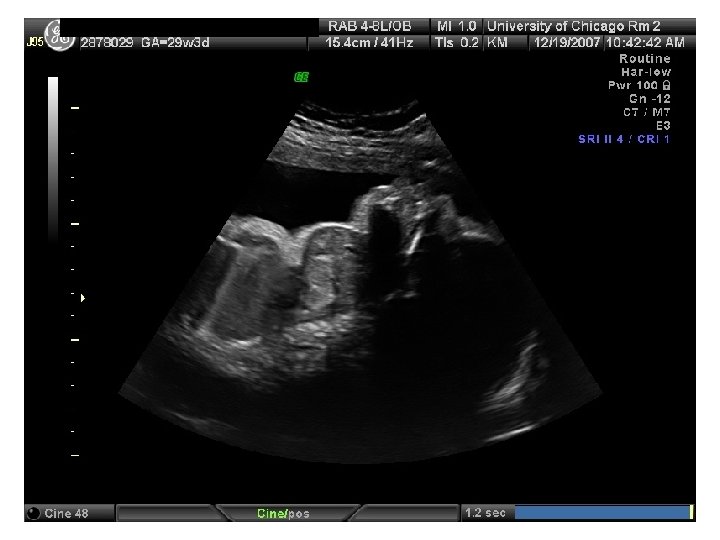

QUIZ What is Your Diagnosis? Case: Patient J. F. 30 years old, at 32 week gestation. Presented with the following pictures.

Answer: a) Trisomy 21 b) Non-immune Hydops c) Paravo virus Infection